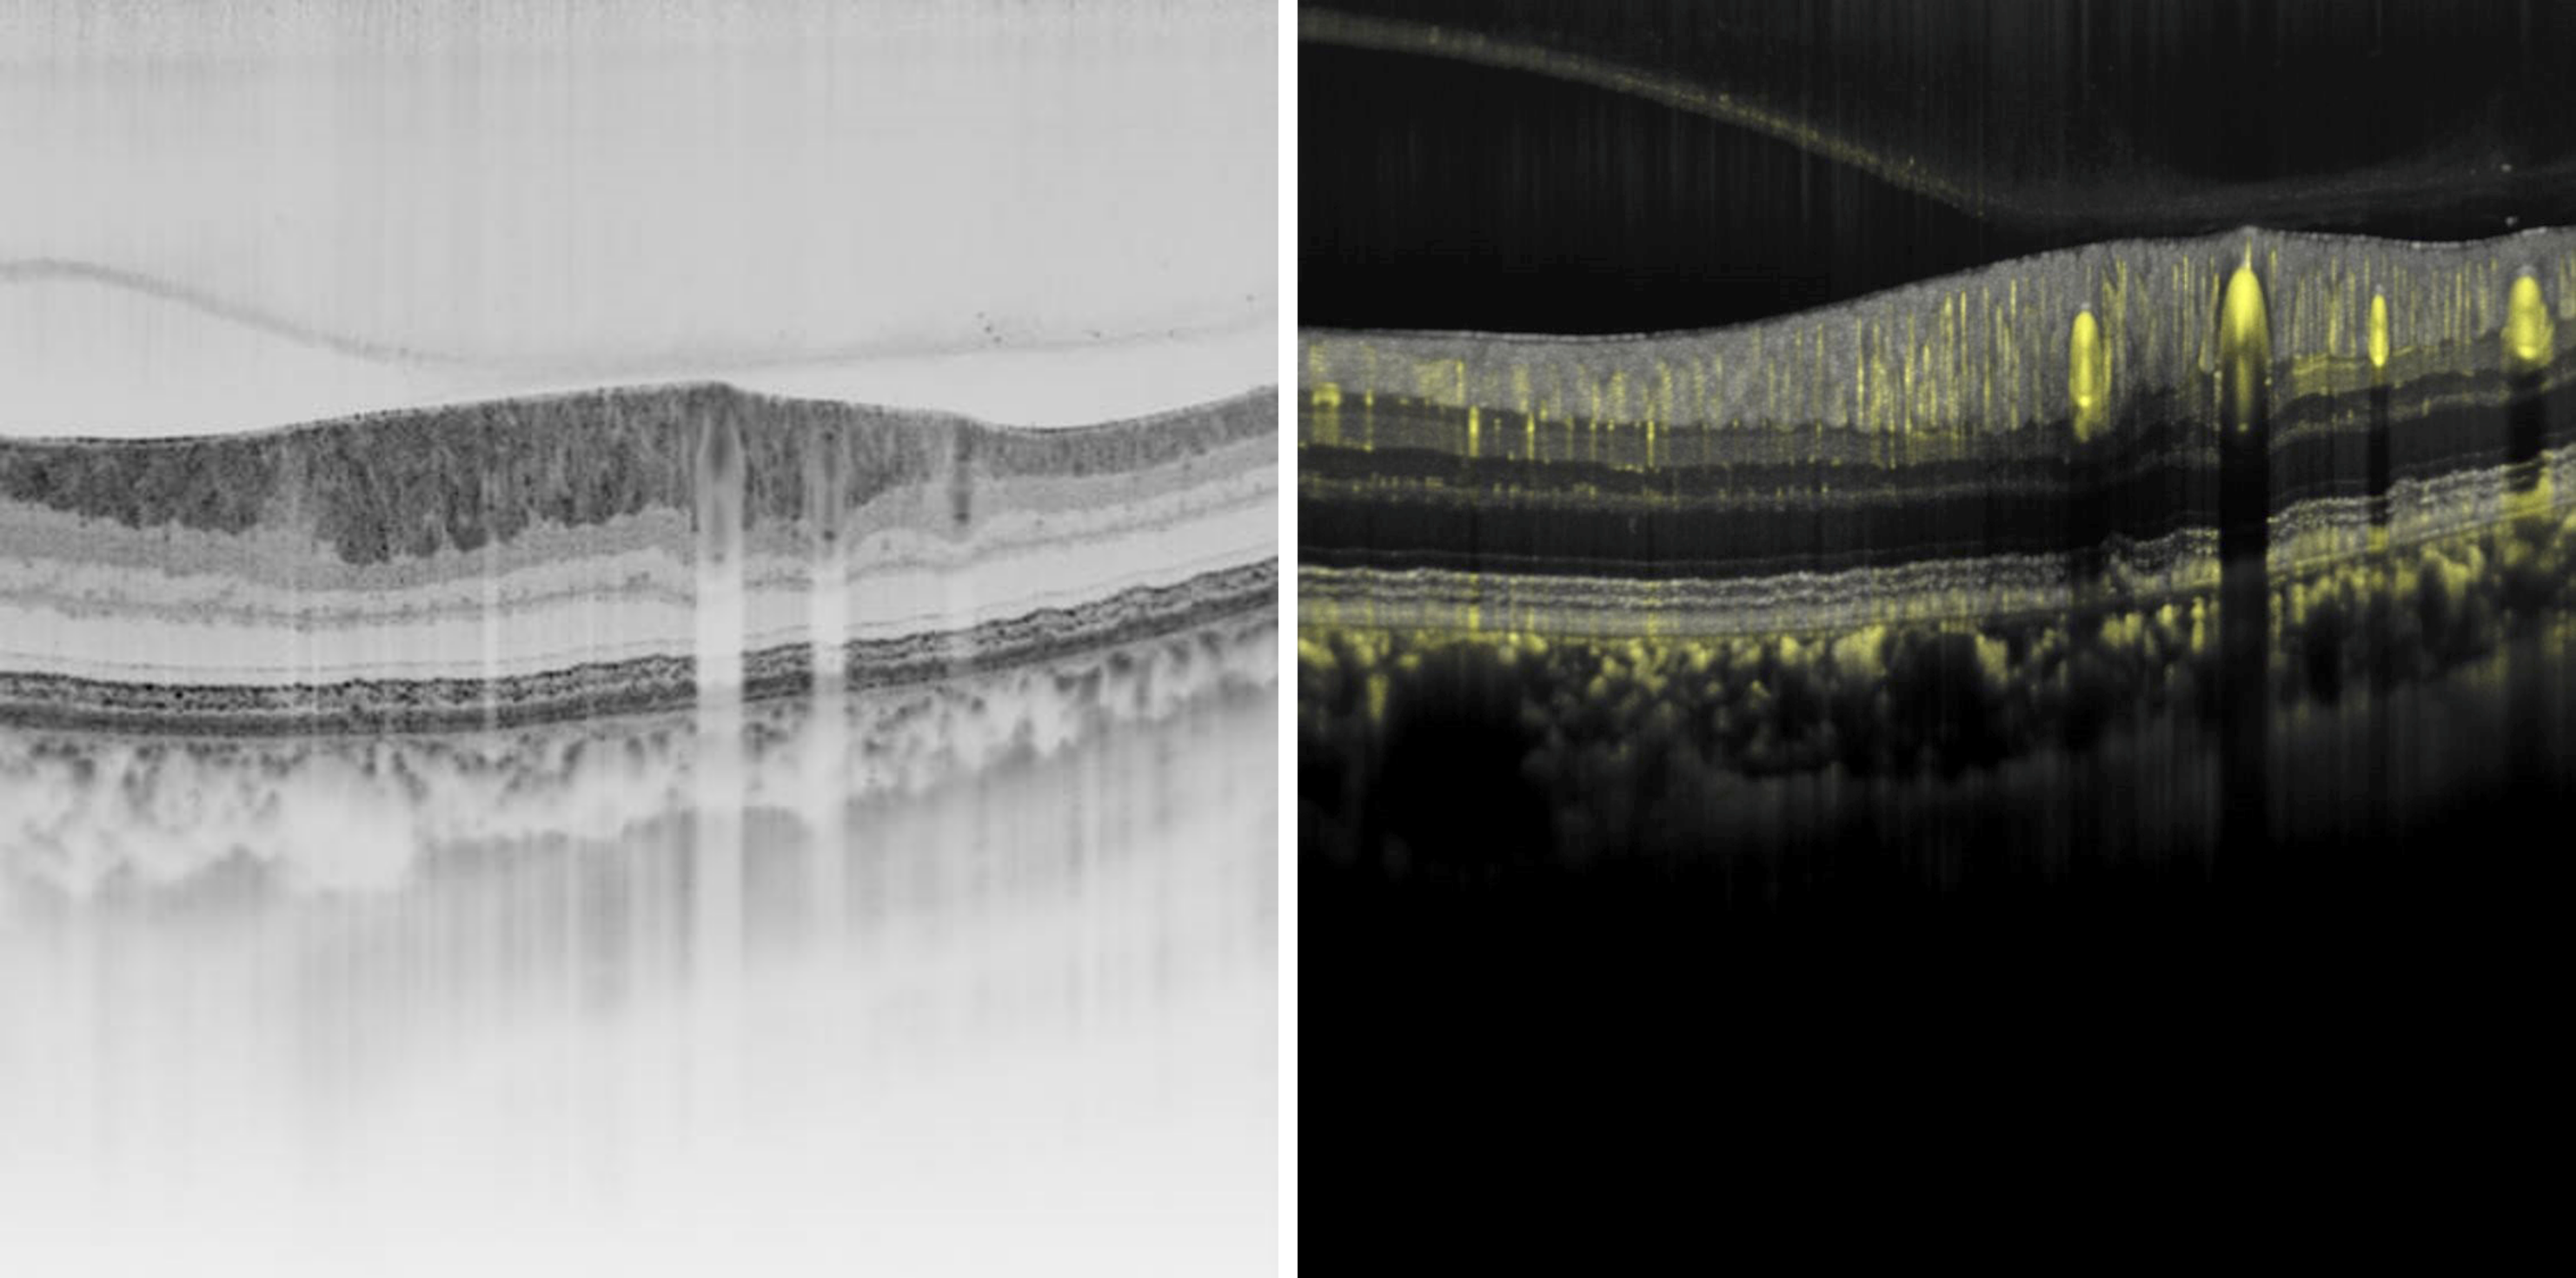

High-resolution structural and vascular OCT imaging of the retina

Heidelberg Engineering has a strong background of developing imaging solutions that support advancements in ophthalmic science and lead to tangible benefits in clinical diagnostics and patient care. The imaging technologies presented at ARVO include high- resolution structural and vascular OCT, swept-source OCT applied to the anterior segment, and novel applications for imaging patients in a supine position. Delegates can also learn more about research being carried out in fluorescence lifetime imaging, OCT- guided selective retinal laser therapy and phenotyping glaucoma.